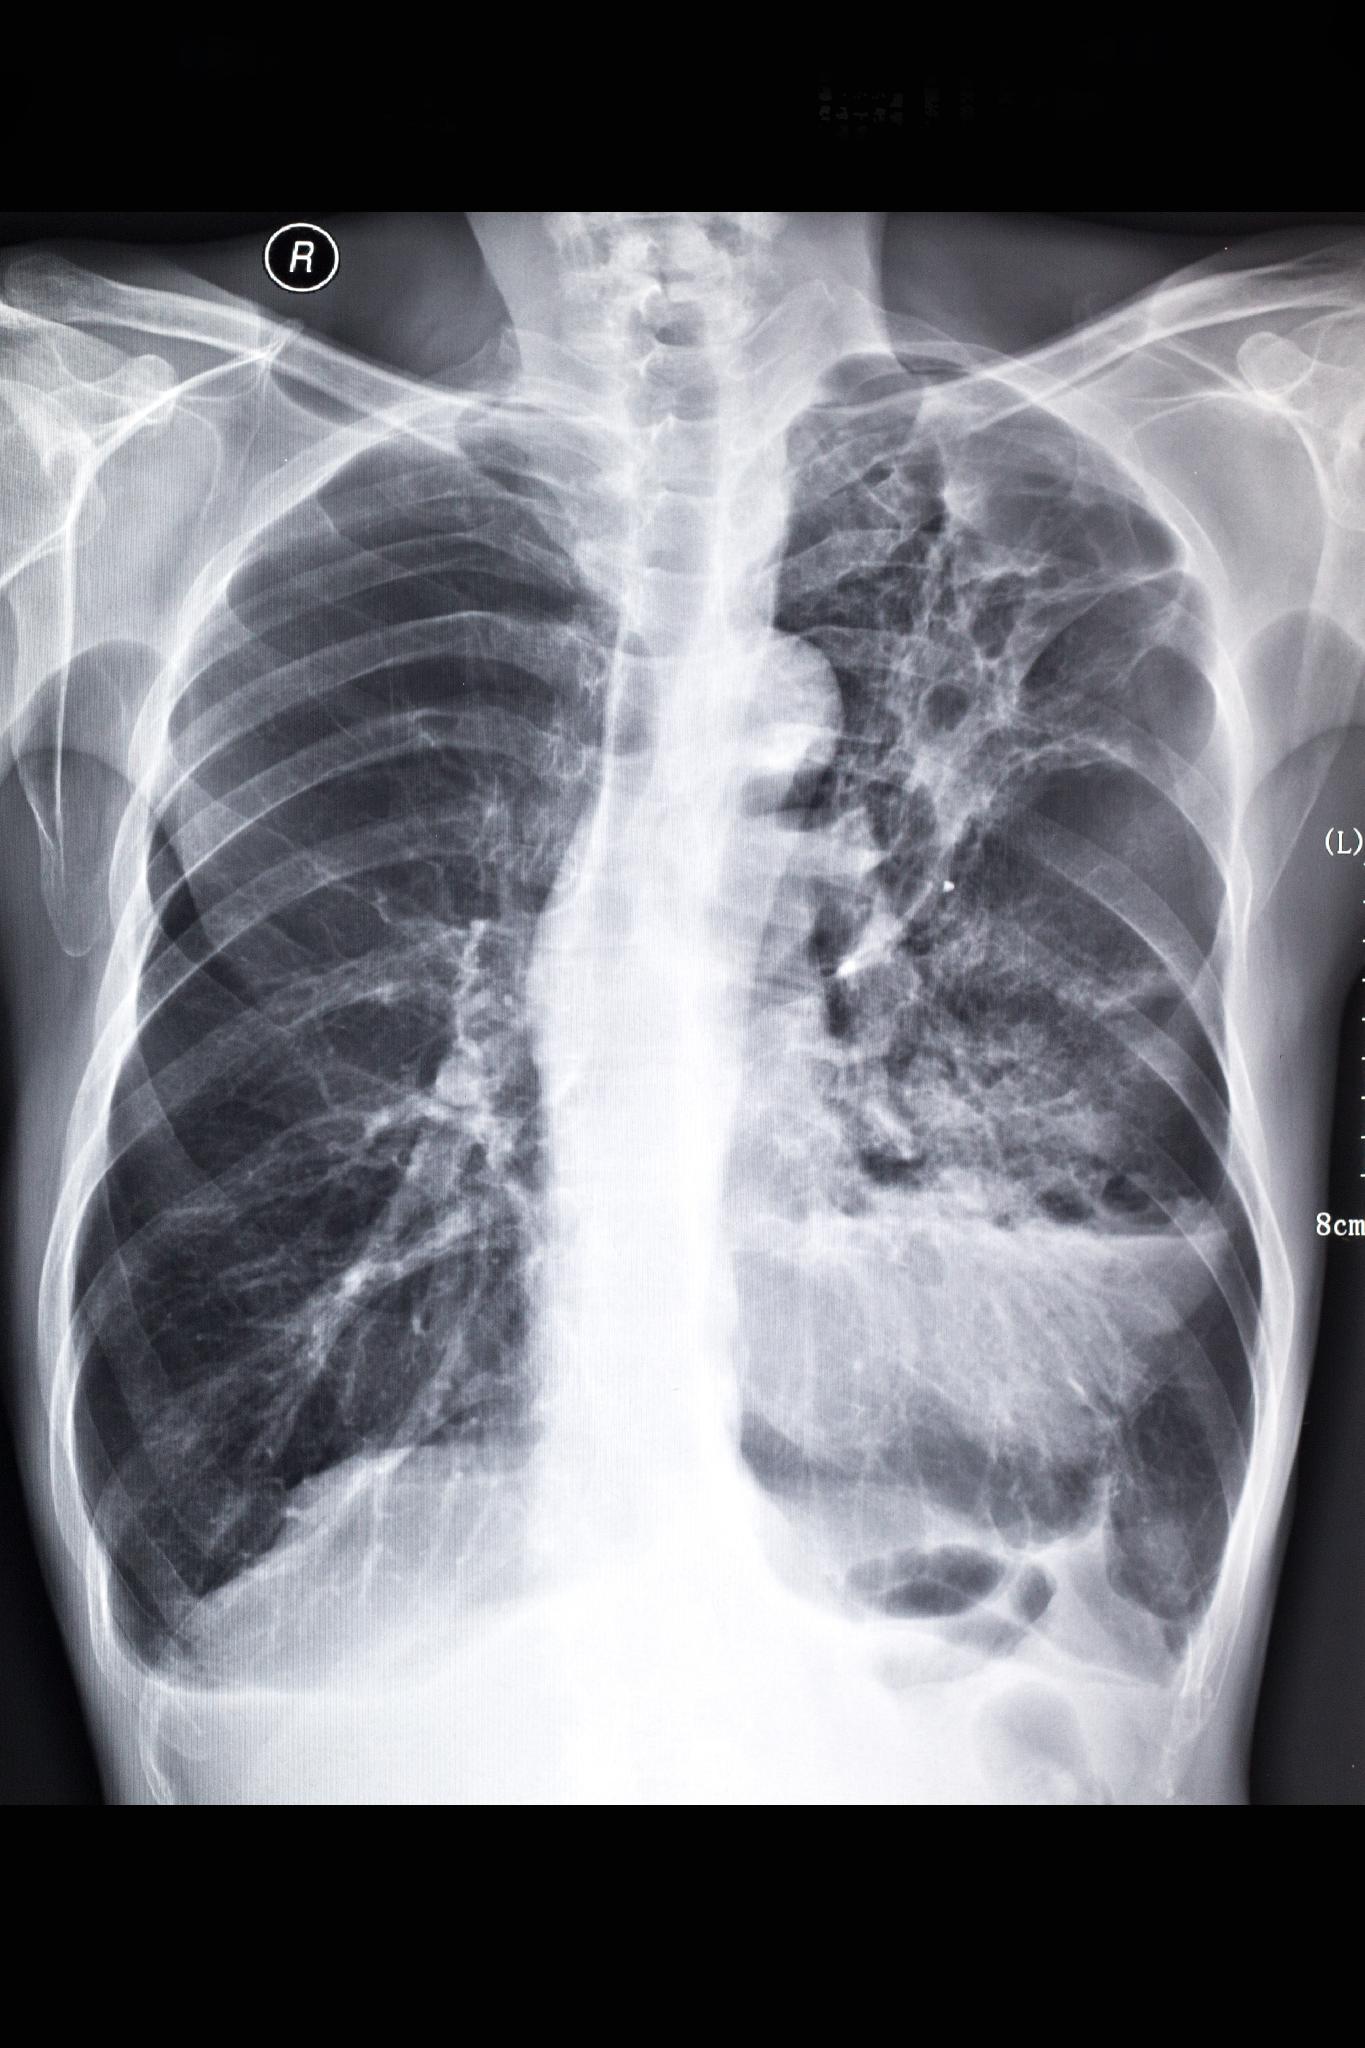

_右肺纖維化真實案例胸片